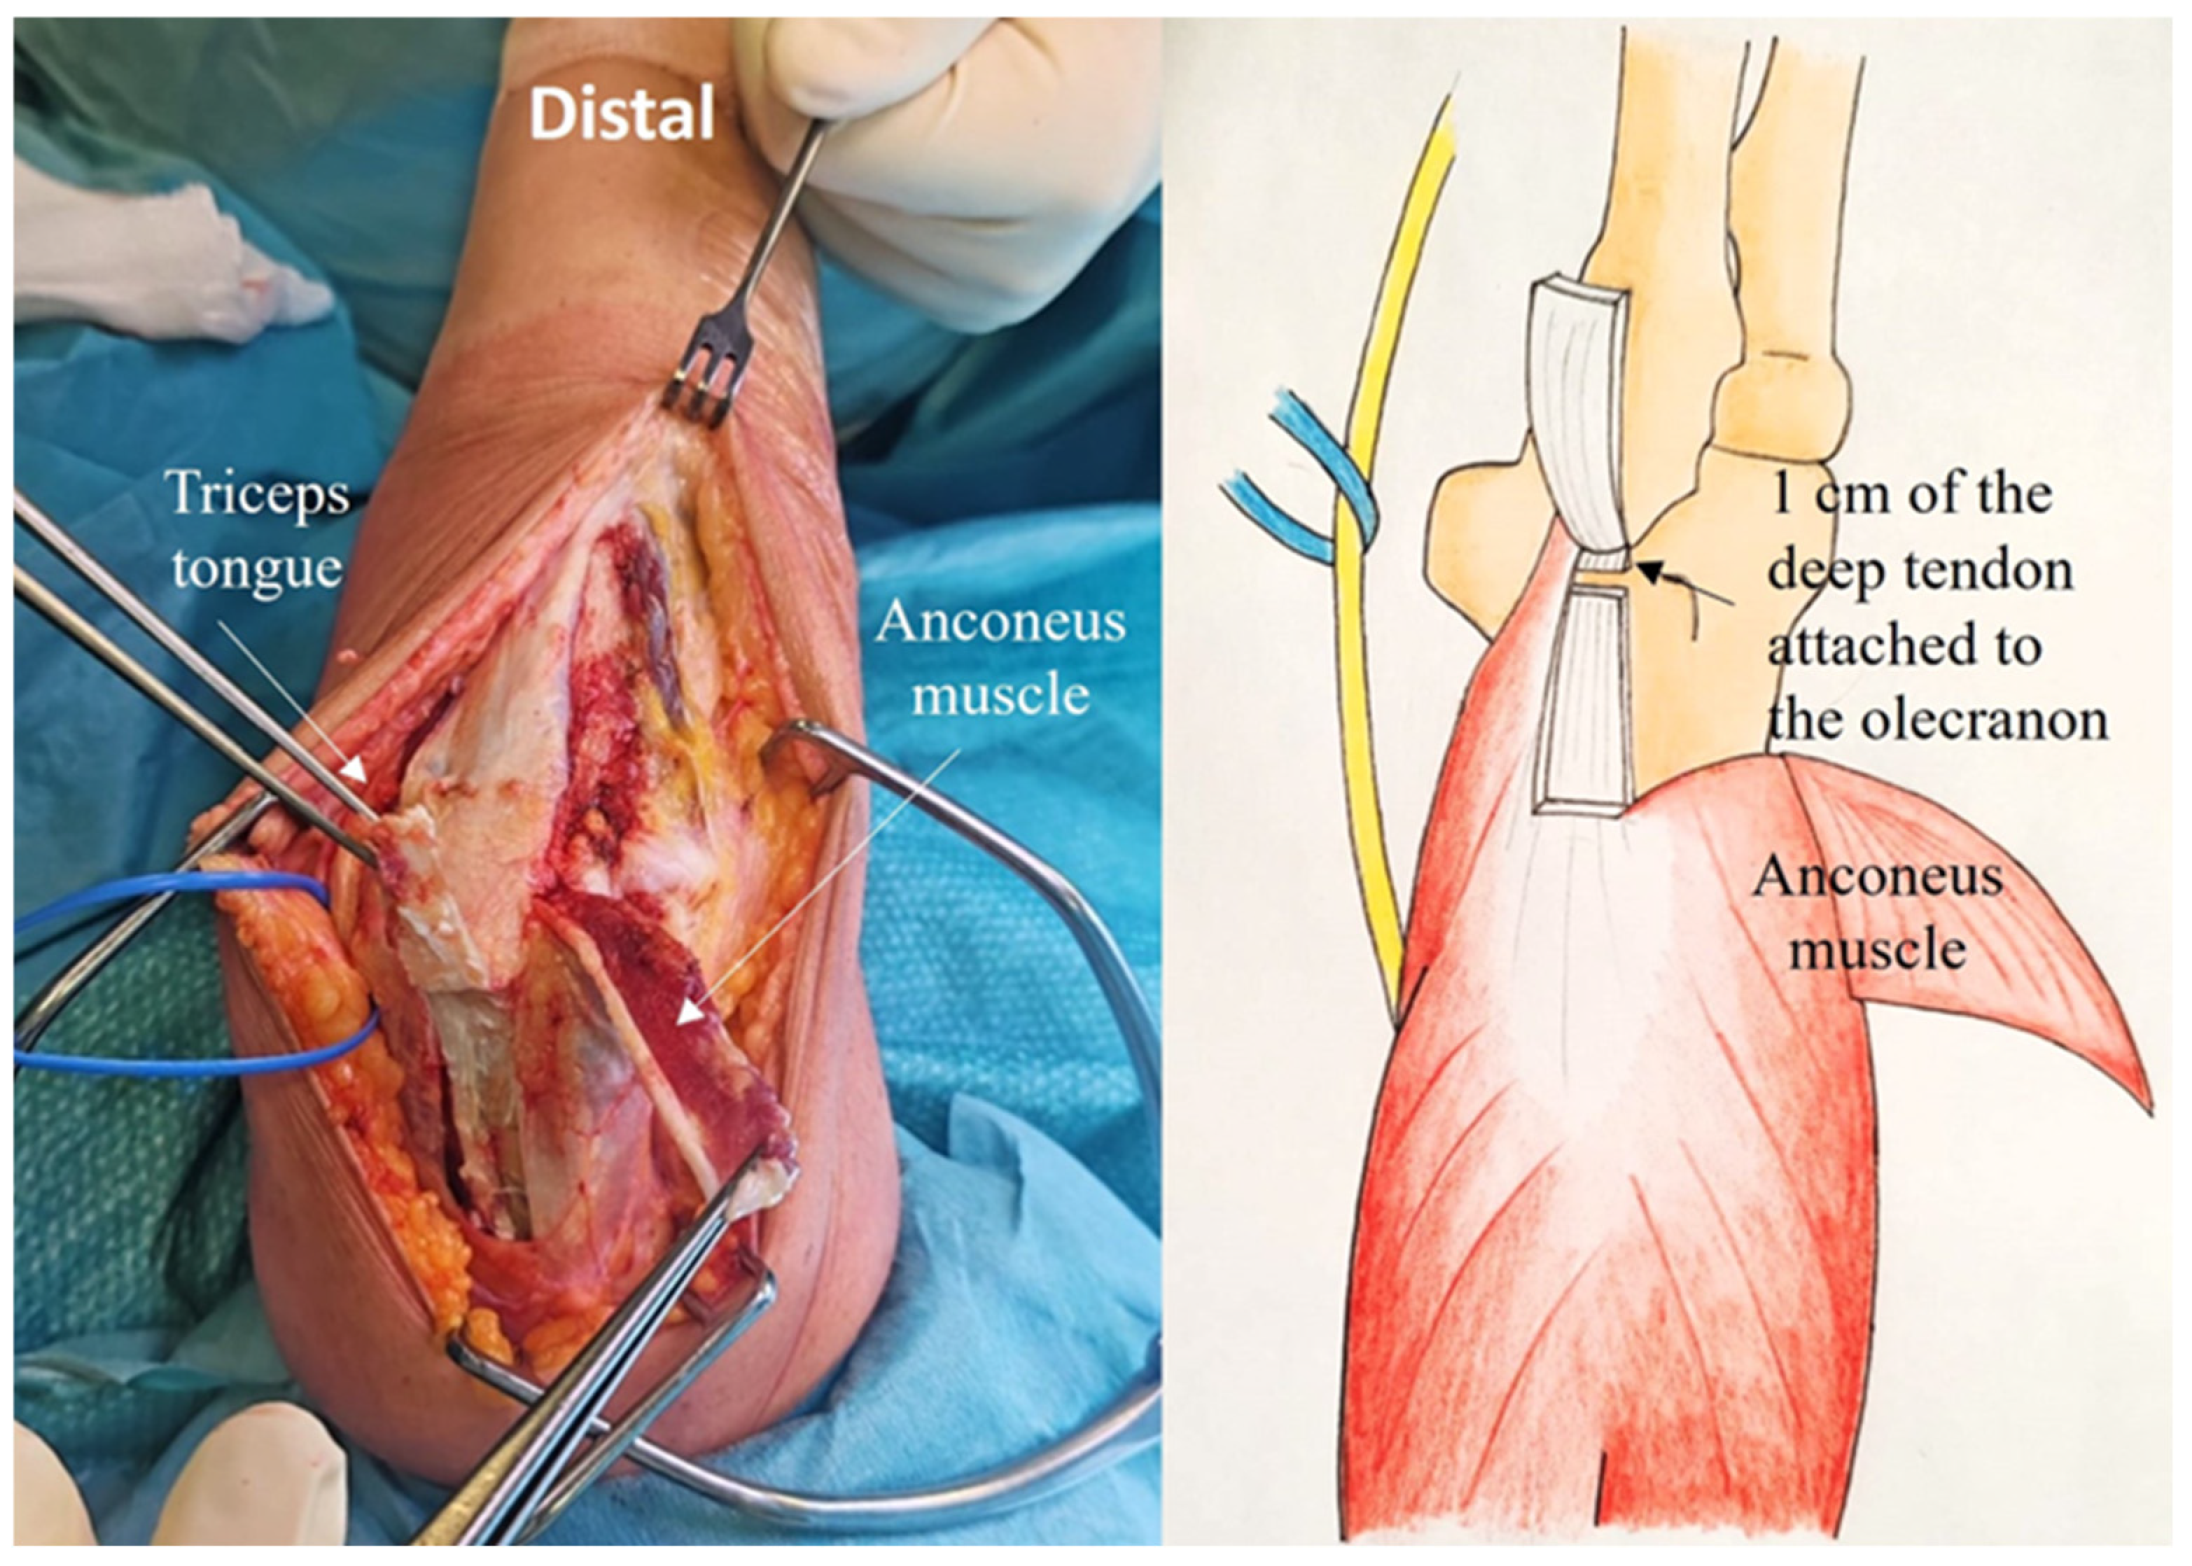

2.4. Development of the ARTT Approach